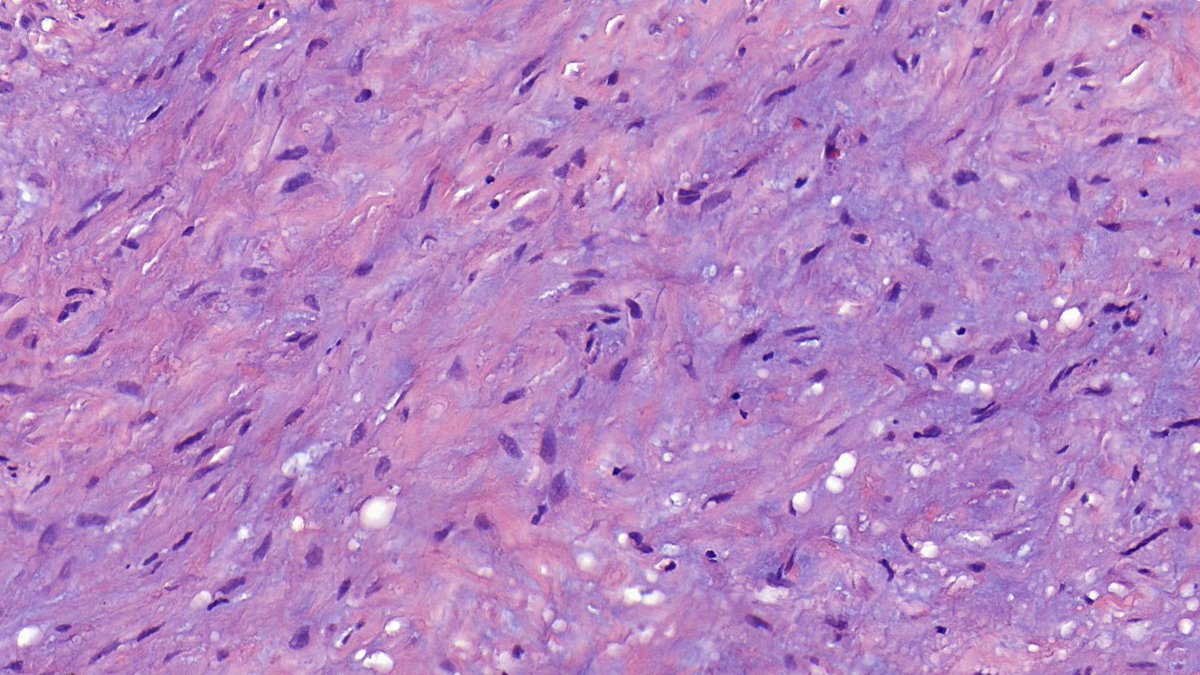

SNO AANP USCAP Malnati Brain Tumor Institute at Northwestern Northwestern Pathology Neurosurgery at NM CAPathologists BTW, gliosarcoma is a subtype of GBM, basically a microscopic descriptor. Gliosarcoma should NOT be the top-line diagnosis, as it might mislead clinicians and patients into thinking it's a completely different tumor.